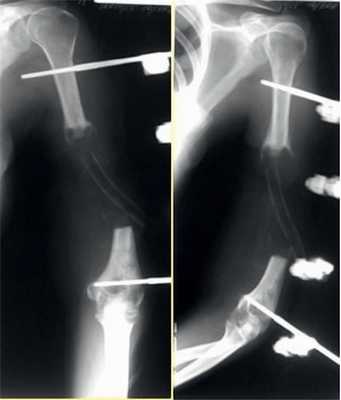

В отделении микрохирургии и травмы кисти ФГБУ «НМИЦ ТО им. Н.Н. Приорова» в период с 2010 по 2017 г. было проведено оперативное лечение 41 пациента (19 мужчин, 22 женщины) с ложными суставами и дефектами плечевой кости с использованием васкуляризованных костных трансплантатов. Средний возраст пациентов составил 41 год (18-65 лет), средний период времени с момента травмы — 2 года и 4 мес (1-8 лет).

До поступления в НМИЦ ТО им. Н.Н. Приорова некоторые пациенты уже были оперированы с применением различных методик наружного и погружного остеосинтеза: среднее количество операций — 2,2 (2-7).

Кровоснабжаемый трансплантат из малоберцовой кости использовался у 38 (93%) пациентов, васкуляризованный трансплантат из медиального мыщелка бедренной кости — у 3 (7%) пациентов (рис. 1). Рис. 1. Распределение пациентов по типу васкуляризованного трансплантата.

Во всех случаях применялся накостный остеосинтез пластиной без контакта пластины с трансплантатом (мостовидная костная пластика).

Консолидация перелома при кровоснабжаемой костной пластике была достигнута в 36 (88%) случаях в течение 4-6 мес (рис. 2): Рис. 2. Результаты оперативного лечения с использованием кровоснабжаемой костной пластикой. в группе применения малоберцового трансплантата консолидация была достигнута в 33 случаях, в группе трансплантата из мыщелка бедренной кости — в 3 случаях.

Клинический пример 1

Пациентка И., 34 лет.

Диагноз: последствия минно-взрывного ранения левого плеча с дефектом плечевой кости, мягких тканей, лучевого нерва. Остеомиелит.

На рис. 3-9 Рис. 3. Пациентка И., 34 лет. Внешний вид до операции. Рис. 9. Внешний вид и функция через год после операции. представлены все этапы обследования и лечения пациентки И.

Рис. 4. Рентгенограмма пациентки И. до операции.